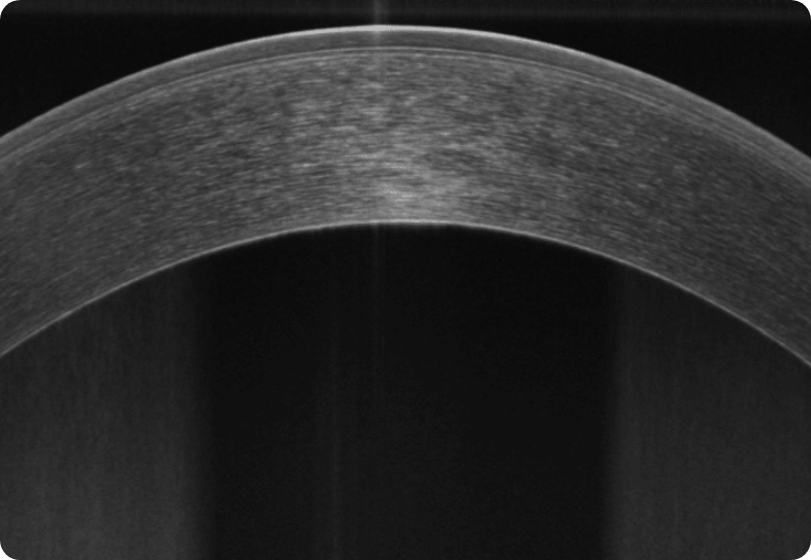

With a unique combination of super-fast scanning at 130,000 scans per second and ultra-high 3μm resolution, this powerful device takes precision, accuracy, and detection of even the finest lesions to a whole new level. The REVO HR is an all-in-one device you can use in a number of ways such as a full colour fundus camera or as a combo, providing simultaneous OCT and fundus images for high quality OCT imaging, including OCT-A.

3μm Axial Resolution

A.I. DENOISE

An advanced artificial intelligence (AI) algorithm removes noise from the tomogram for the highest image quality.